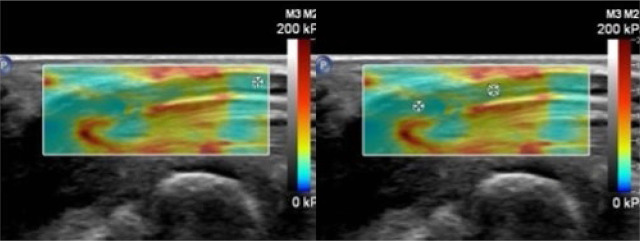

Material and methods: A prospective case-control study was conducted on 50 participants (50 wrists), including 25 carpal tunnel syndrome cases diagnosed by nerve conduction study and 25 healthy controls. Shear wave elastography assessed the stiffness of the median nerve at three locations: outside the carpal tunnel, at the inlet, and at the outlet. Cross-sectional area measurements were also obtained using B-mode ultrasound. Receiver operating characteristic curves were used to evaluate diagnostic performance.

Results: Shear wave elastography and cross-sectional area demonstrated high diagnostic accuracy for carpal tunnel syndrome, with a cut-off value of ≥63.5 kPa inside the tunnel (mean of inlet and outlet values) and a cross-sectional area cut-off of ≥0.08 cm2 at the inlet of the tunnel offering optimal performance. While cross-sectional area provided high sensitivity, shear wave elastography showed superior specificity; their combination improved overall diagnostic accuracy. Shear wave elastography values did not significantly differ across carpal tunnel syndrome severity grades based on nerve conduction study (p >0.05). However, shear wave elastography at the tunnel inlet differentiated severe carpal tunnel syndrome from non-severe cases (p = 0.045), with a cut-off of ≥126 kPa predicting severe carpal tunnel syndrome with 100% sensitivity, 77% specificity, and an area under the receiver operating characteristic curve of 0.871.

Conclusions: Shear wave elastography is a reliable, non-invasive modality for carpal tunnel syndrome diagnosis, offering excellent specificity, particularly when combined with cross-sectional area. Additionally, shear wave elastography at the tunnel inlet may help identify severe carpal tunnel syndrome, supporting timely clinical decision-making and prioritization of intervention.